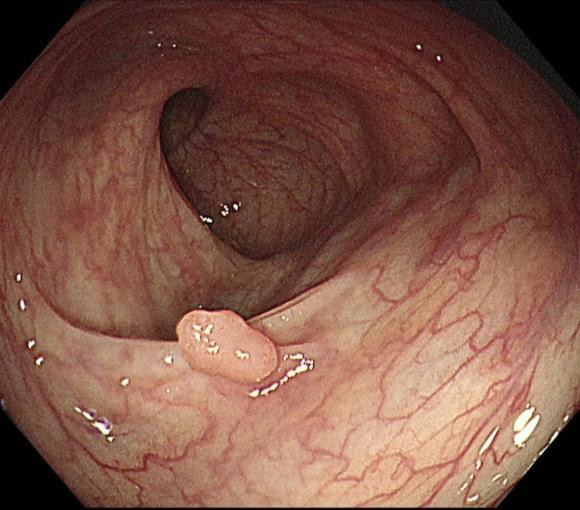

Polyp đường ruột có phải cắt không?

Bản thân polyp không phải là ung thư, nhưng chúng có thể trở thành ung thư, một khi phát hiện ra polyp đường ruột, tốt nhất là nên cắt bỏ chúng càng sớm càng tốt để tránh các bệnh khác hoặc biến đổi thành ung thư.

Với sự phát triển của kỹ thuật y học, người ta đã có thể dùng bẫy để cắt dưới ống nội soi, hoặc điều trị bằng đốt điện, laser rất an toàn, hiệu quả, người bệnh ít đau, không cần phải mổ mở lồng ngực, phẫu thuật nội soi, hoặc thậm chí nhập viện.

Nhưng không phải tất cả polyp đều trở thành ung thư. Polyp đại trực tràng được chia theo tính chất, phổ biến là polyp viêm và polyp tuyến, loại thứ nhất là do tăng sản và viêm nhiễm đường ruột gây ra, hầu như không ác tính.

Do đó, thông thường khuyến cáo rằng một khi polyp đường ruột được tìm thấy, chúng nên được cắt bỏ và kiểm tra giải phẫu bệnh.